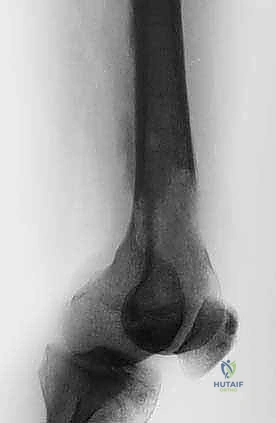

* عظم الفخذ (Femur): أطول وأقوى عظام الجسم، وإصابته تهدد قدرة المريض على المشي.

* عظم العضد (Humerus): يؤثر بشكل مباشر على استخدام الذراعين.

1. حدوث كسر مرضي فعلي في عظم رئيسي (مثل الفخذ).

1. التثبيت الوقائي الداخلي (Prophylactic Internal Fixation)

إذا أظهرت الأشعة أن العظم ضعيف جداً وعلى وشك الانكسار، يقوم الدكتور هطيف بوضع أسياخ نخاعية معدنية (Intramedullary Nails) أو شرائح ومسامير متطورة داخل العظم لتدعيمه ومنع الكسر قبل حدوثه. هذه الجراحة الاستباقية توفر على المريض آلاماً مبرحة ومضاعفات خطيرة.

| جسم عظم الفخذ أو الساق | كسر مرضي كامل أثناء التحميل. | التثبيت بمسمار نخاعي تشابكي (Intramedullary Nailing). |

| الطرف العلوي (عظم العضد) | فقدان وظيفة الذراع، ألم شديد. | التثبيت بشرائح ومسامير أو مسمار نخاعي مع استخدام أسمنت عظمي. |